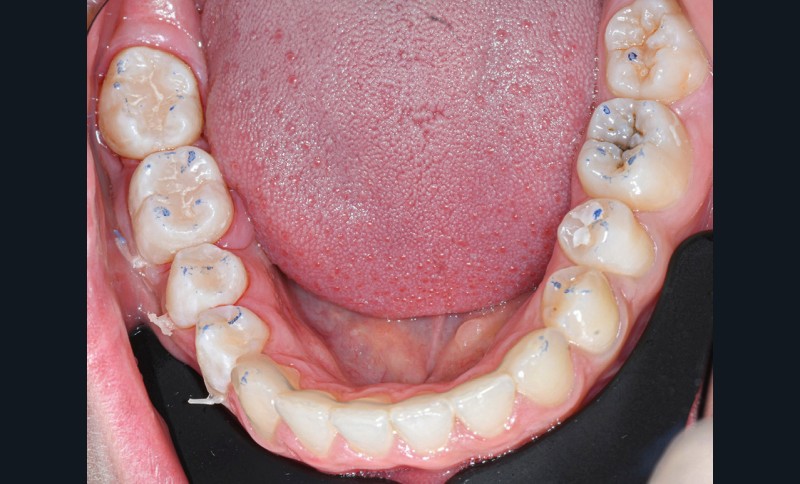

Nous détaillons la technique à travers le cas d’une jeune fille de 18 ans présentant des lésions carieuses sur quatre dents (fig. 1 à 14).

Cette technique de tampon occlusal est indiquée lorsque la face occlusale de la dent à reconstruire est fonctionnelle. Elle évite les multiples incréments occlusaux de résine composite. En contrepartie, elle demande un peu d’entraînement, notamment pour bien replacer le tampon et doser correctement la quantité de résine composite à appliquer avant de tamponner la face occlusale. Néanmoins, une fois maîtrisée, elle est rapide et offre une grande reproductibilité de la situation occlusale de départ en s’évitant les potentielles retouches fastidieuses de fin de séance.